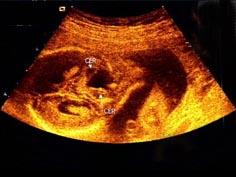

问题 胎儿头颅部超声检查如图,最可能的诊断是 ( )

选项 A、孔洞脑 B、小脑蚓部缺损 C、脑积水 D、先天性蛛网膜囊肿 E、正常声像图

答案 B